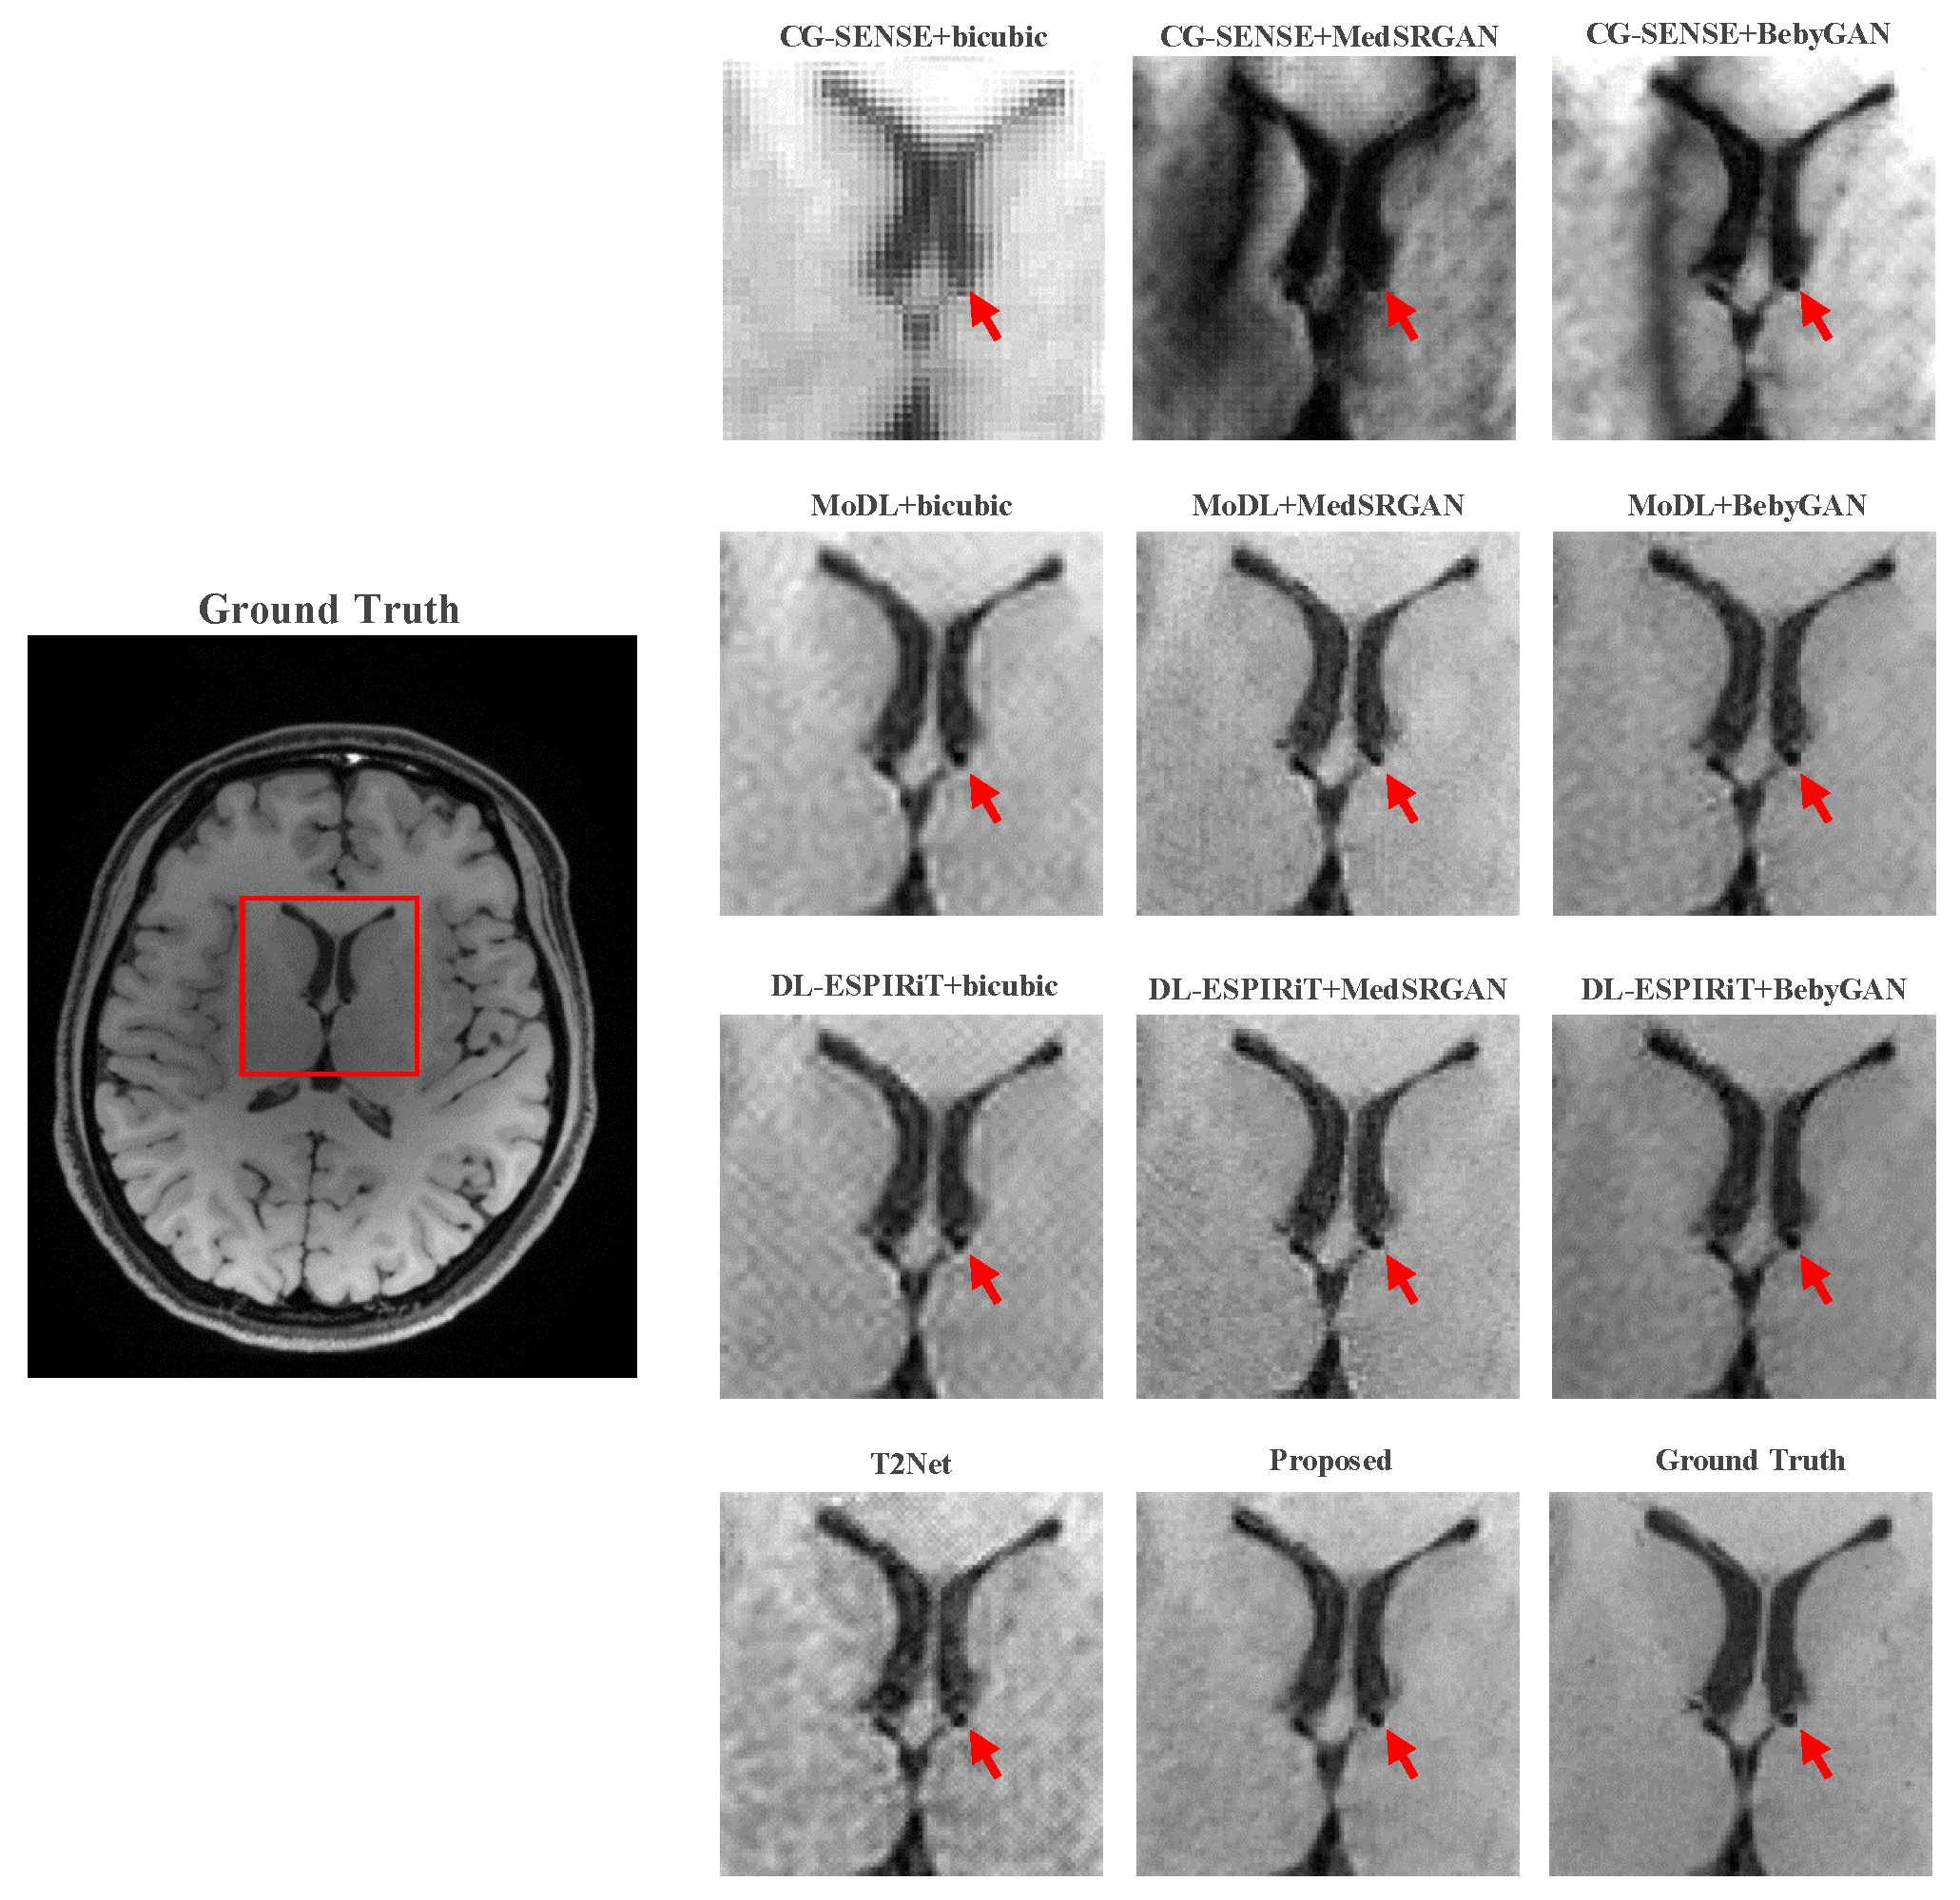

For a more intuitive comparison, we provide visual comparisons for each method. In Figure 5 and Figure 6, we illustrate the axial and sagittal views of the 2D brain dataset, respectively. In Figure 7 and Figure 8, we display the brain image and neck image of the 3D VWI dataset. For each method, we show the restorations along with the corresponding error maps. The images are placed on the left, the error maps on the right, and the PSNR and LPIPS metrics of each image are shown at the bottom right corner. From the error maps, it is evident that our proposed method consistently produces high-quality results with improved visual fidelity and better retention of structural information compared to the other methods.

Figure 9 and Figure 10 present the zoomed-in images of the enclosed parts in the ground truth. Our proposed method can faithfully recover the fine structures, as indicated by the red arrows, and successfully preserve the image contrast, as pointed out by the yellow arrow. The high-fidelity restoration achieved by our method in these zoomed-in regions further demonstrates its ability to faithfully recover fine details and enhance image quality.

Figure 9. Zoomed-in view of the brain dataset comparison experiment.